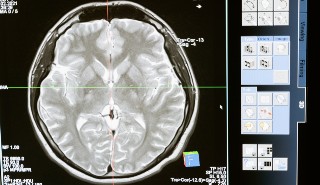

Alzheimer’s Disease could be caused by damage to a protective barrier in the body that allows fatty substances to build up in the brain, newly published research argues.

A new explanation called the ‘Lipid Invasion Model’, argues that lipids entering the brain due to damage to the blood brain barrier - a dense system of small blood vessels in the brain that allow only a small number of essential substances to pass through - is the determining cause of the degenerative disease that affects millions worldwide.